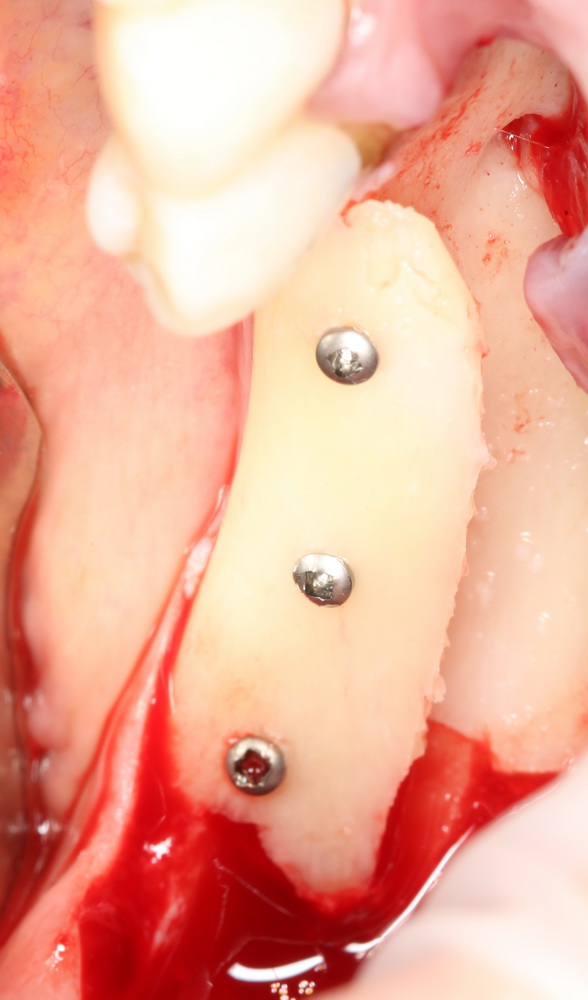

Итого, наиболее оптимальным в данной ситуации оказалась направленная тканевая регенерация с использованием барьерных мембран. В качестве барьерной мембраны у нас будет Geistlich BioGide. Ее очень легко адаптировать и позиционировать:

А в качестве трансплантата — аутокостная стружка, которую я насобирал заранее из области угла нижней челюсти:

Начну с того, что BioGide — это лучшее, что есть сейчас на рынке, а остальные мембраны ей завидуют. Как и в случае с макродизайном имплантов, именно физические свойства определяют как удобство использования, так и возможность достижения нужного результата. Прочность, эластичность, легкая адаптация и адгезия делают ненужными использование фиксирующих пинов. Мы просто закрываем мембраной графт — и все, можно накладывать швы:

В другом ракурсе видно, какой объем тканей мы восстанавливаем: